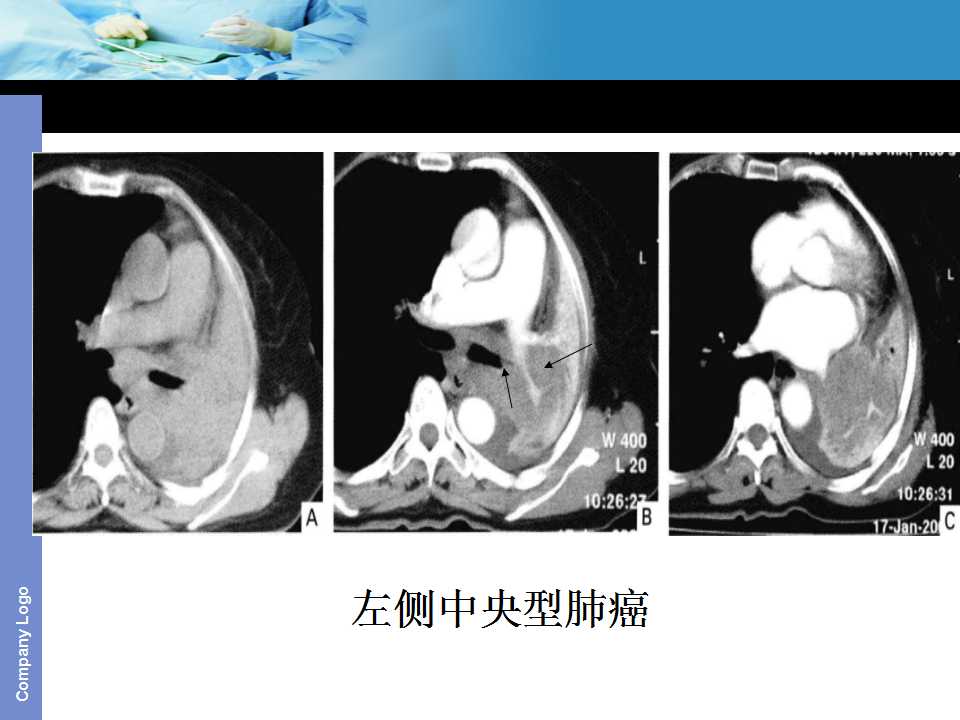

肺癌影像诊断